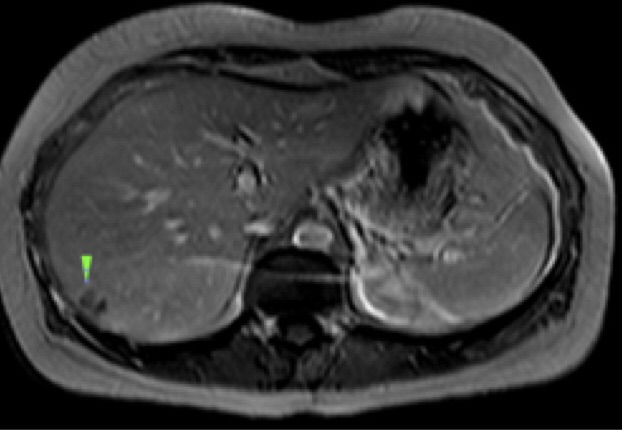

Методы динамического контрастирования печени на МРТ

Раздел: Снимки-подсказки